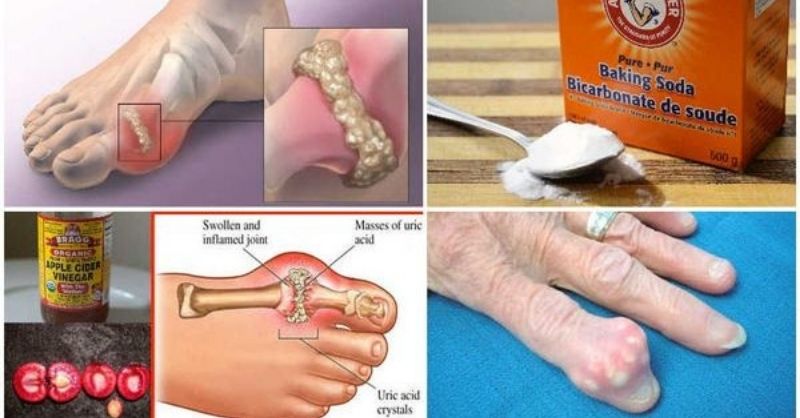

How to Prevent Gout and Joint Pain by Removing Uric Acid Crystallization

Gout and joint pain can be extremely uncomfortable, especially for individuals aged 45 to 65. If you’re experiencing swelling, stiffness, and acute pain in your smaller foot bones,...